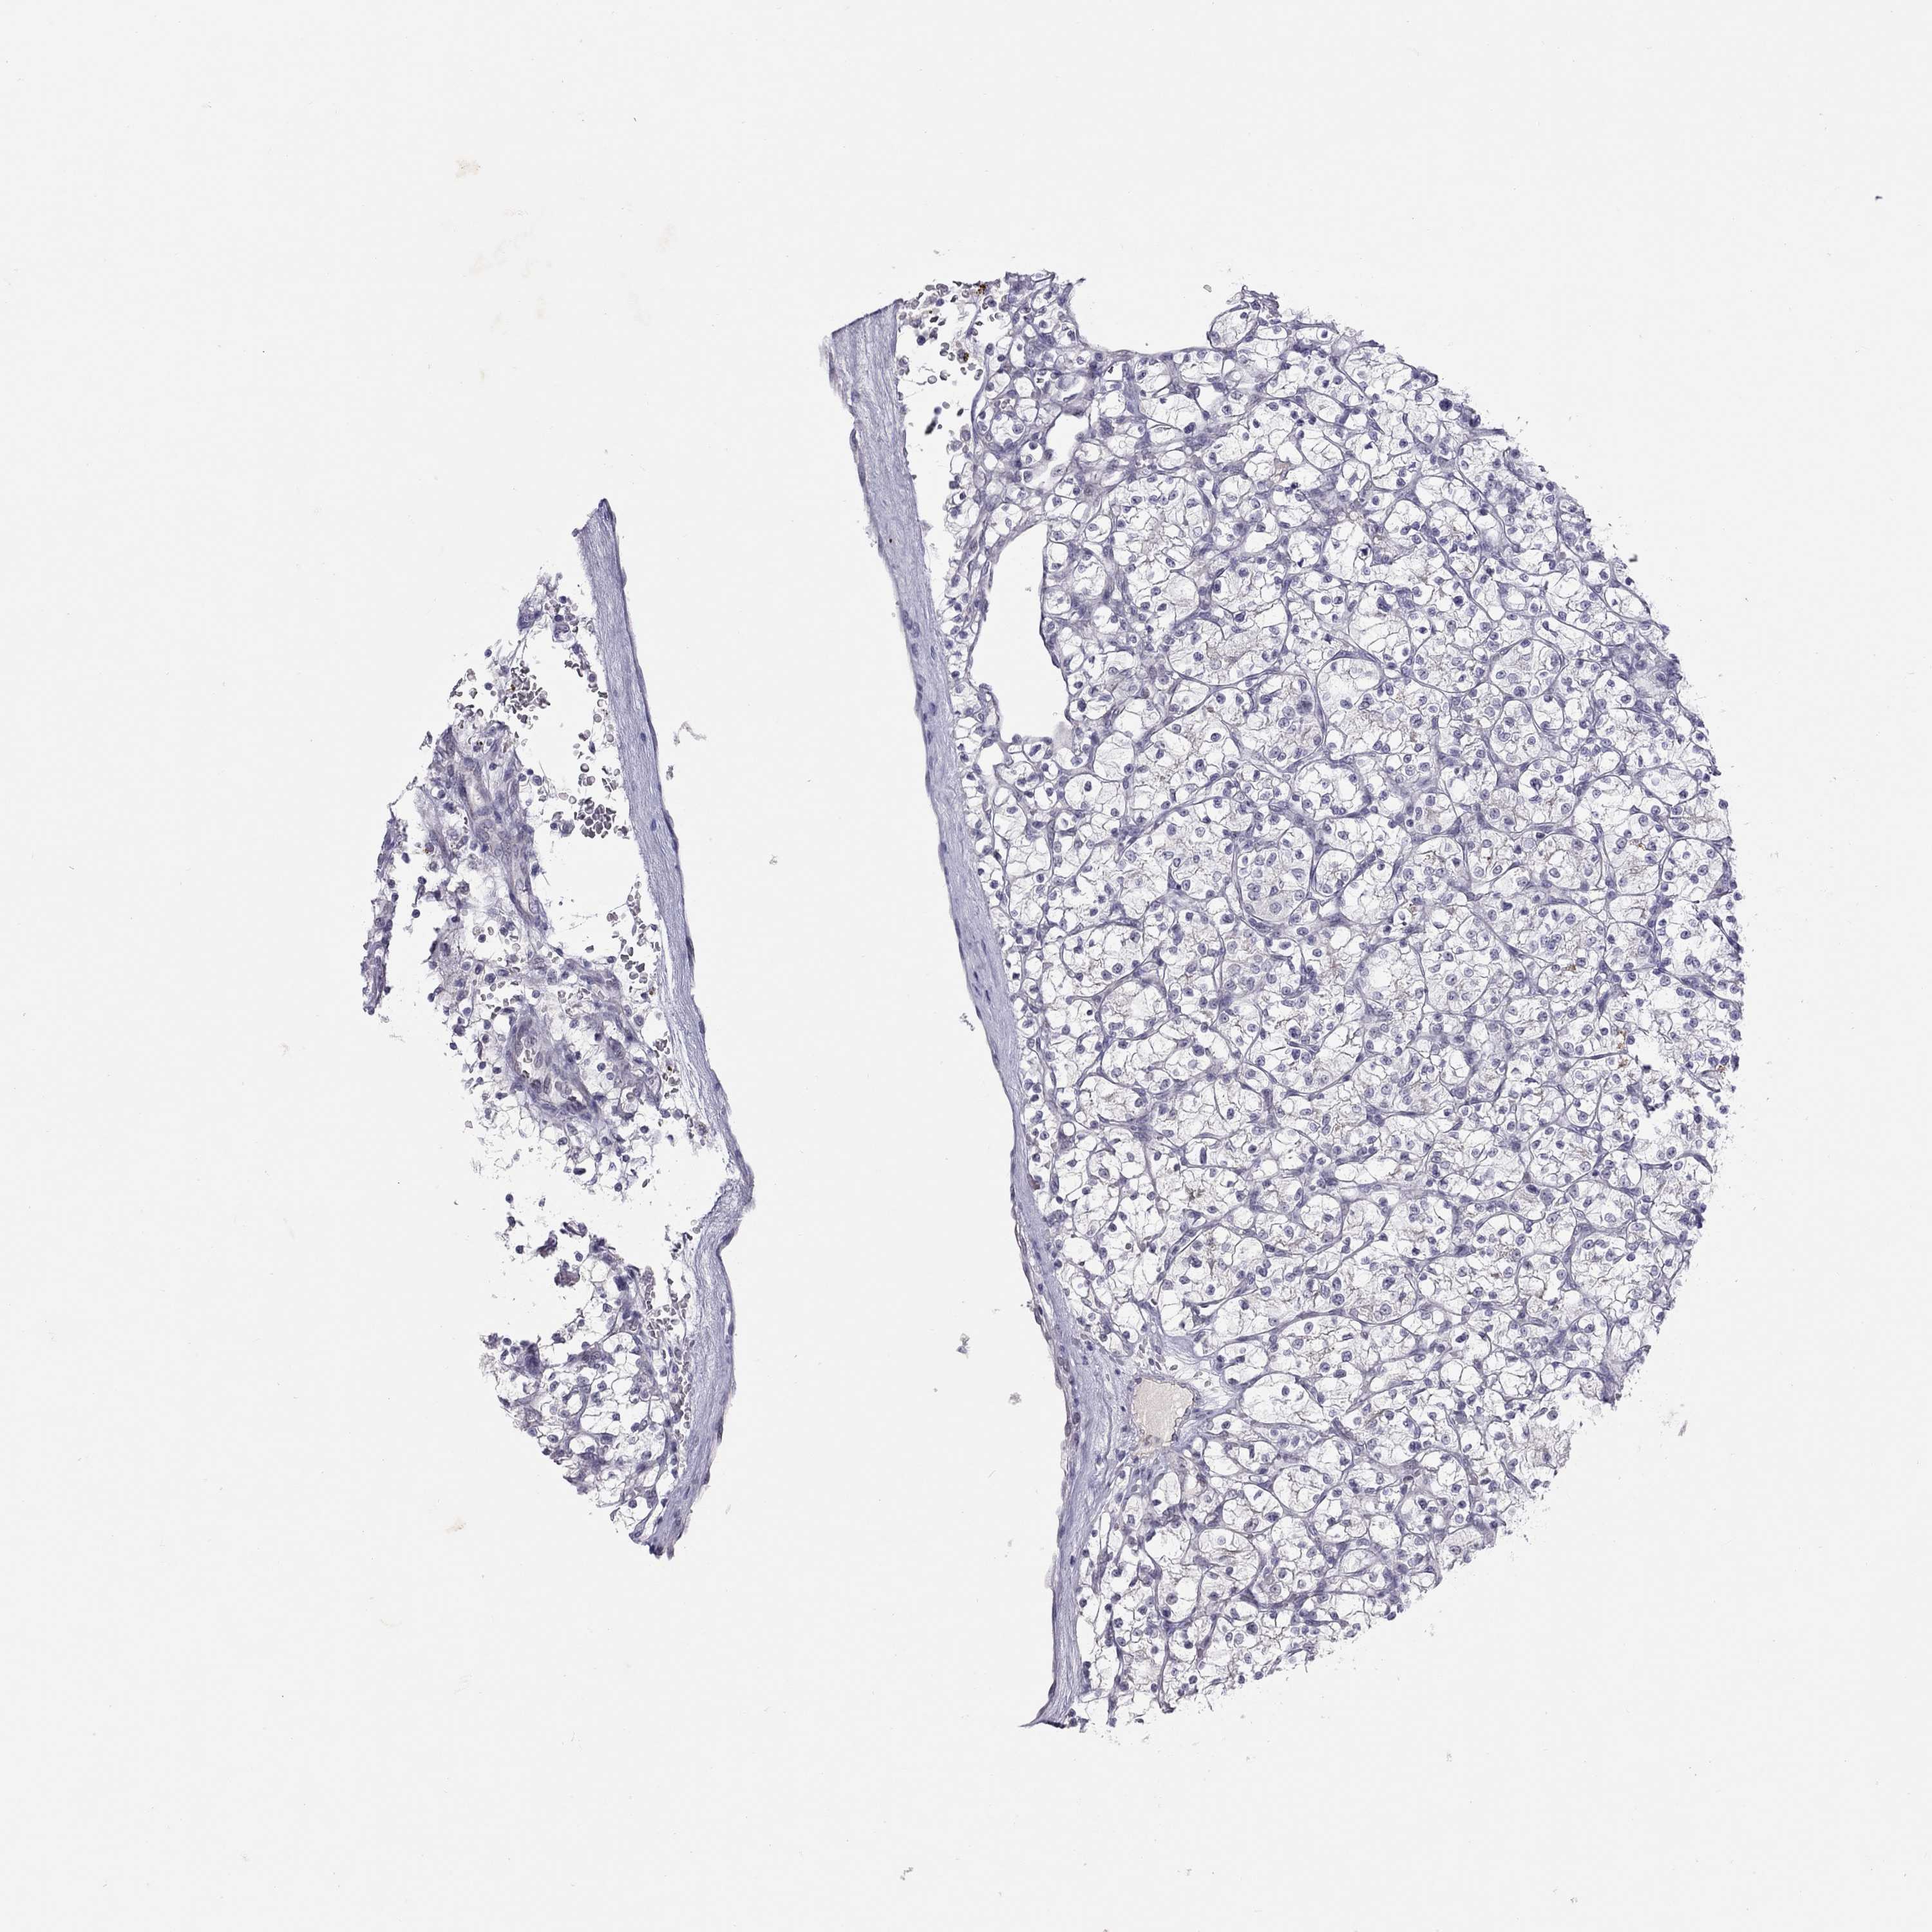

KICH TCGA KIRC TCGA KIRC VALIDATION KIRP TCGA PROTEIN RCC CPTAC PROTEIN EXPRESSION

Kidney renal clear cell carcinoma